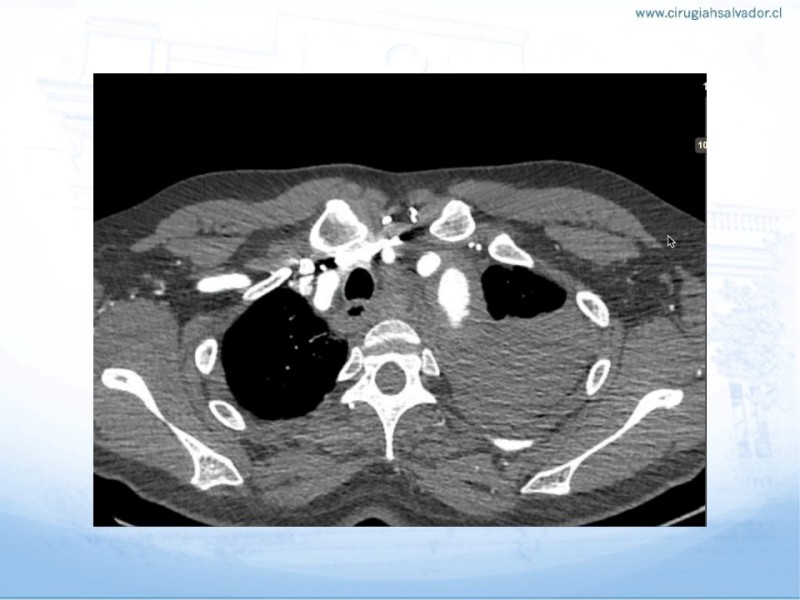

Síndrome aórtico agudo

Cirugía Cardíaca

| Autor: Dr. Nicolás Pimentel P.